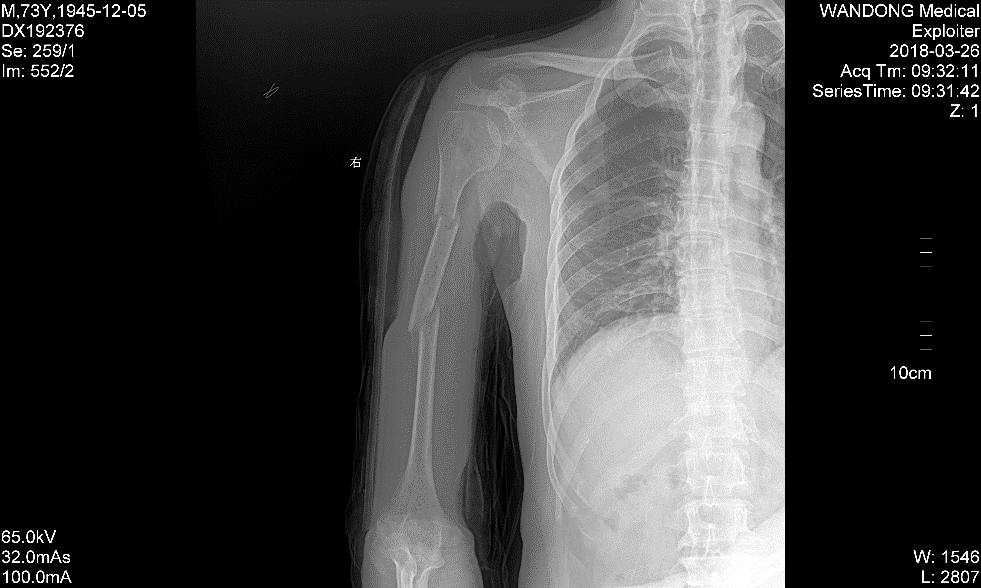

经过半个月小心治疗后,李大伯的手臂肿胀消退,伤情稳定下来,而后继续绑固治疗并辅助相关药物。8周后再次拍片,伤肢已经没有疼痛感,经拍片显示有较多骨痂形成,可以拆除夹板了。又再次小心嘱咐李大伯,要逐渐加强伤肢的功能训练,避免过早用力,估计半年左右就能痊愈了。